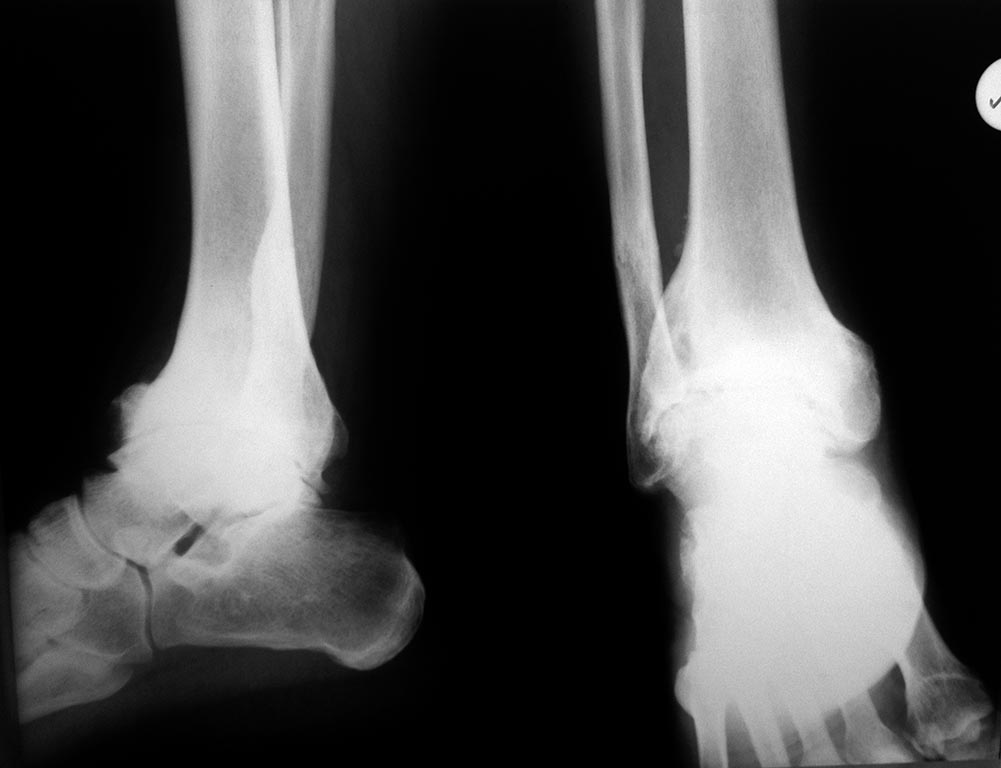

Подтаранный сустав выглядит очень прилично. Его надо сохранить. Гвоздь это замыкание 2 суставов.

Мы бы не стали штифтовать. Можно и открыто винтами зафиксировать, но подтаранный сустав сохранить, при артродезированноь голеностопе он в биомеханике стопы очень нелишний.

Уважаемый В.Машталов, возможно выполнение артродеза голеностопного сустава штфитом с сохранением голеностопного сустава. В нашей клинике недавно была выполнена операция у больного с посттравматическим артрозом, артродез выполнен штифтом "Эксперт" с блокированием в теле таранной кости(винты с угловой стабильностью). Ниже привожу описание случая.

На рентгенограммах осенью 2012 года имеется несросшийся перелом правой большеберцовой кости в средней трети, перелом нижней трети консолидирован. По поводу несросшегося перелома выполнен демонтаж аппарата Илизарова, остеосинтез штифтом "Эксперт". Впоследствии, у больного имелись боли в голеностопном суставе (при ходьбе и в покое), ограничение амплитуды движений, на рентгенограммах определяется несросшийся перелом диафиза большеберцовой кости.

В связи с чем, в январе 2014 года больному удален штифт, выполнено рассверливание костномозгового канала, реостеосинтез штифтом большего диаметра, артродез правого голеностопного сустава, с костной пластикой. Раны зажили без воспаления. В течение 4х недель после операции передвигался с опорой на костыли, с нагрузкой 25 кг. Сейчас передвигается с опорой 50 кг на правую ногу.